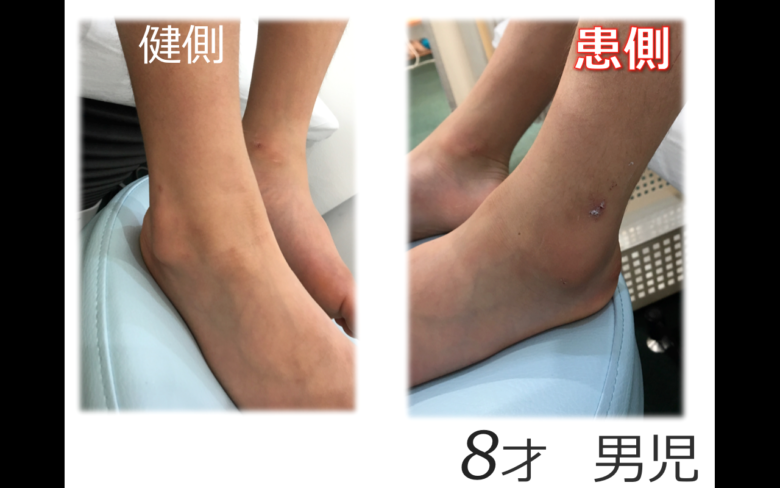

子供さんの足首の骨折

子供さんの足首の骨折

子供さんの足首の骨折

腓骨遠位骨端線損傷 小児の骨折と成人の骨折ではどう違うの 古東整形外科 リウマチ科